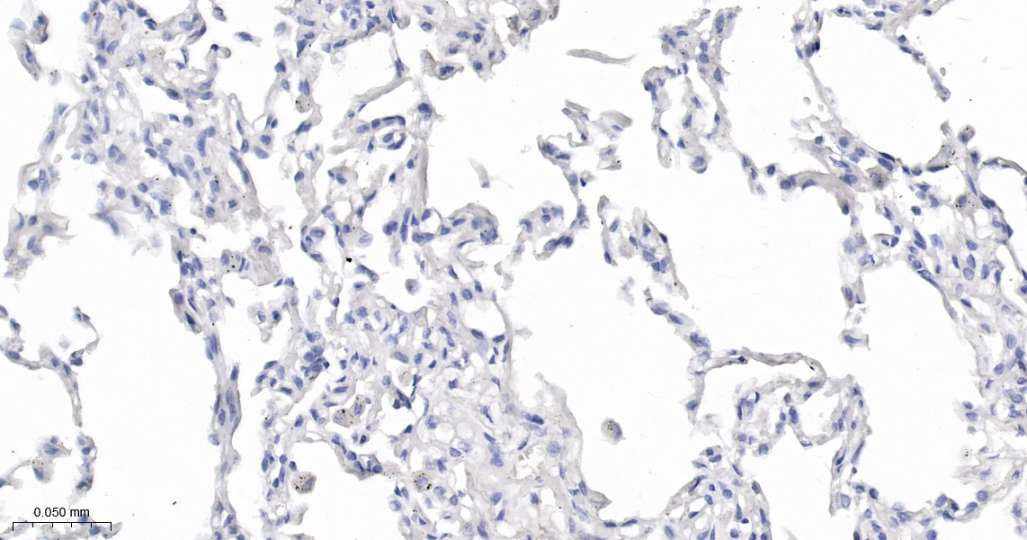

Immunohistochemical analysis of paraffin embedded Human lung tissue slide using IHC0630 (MOG IHC Kit).